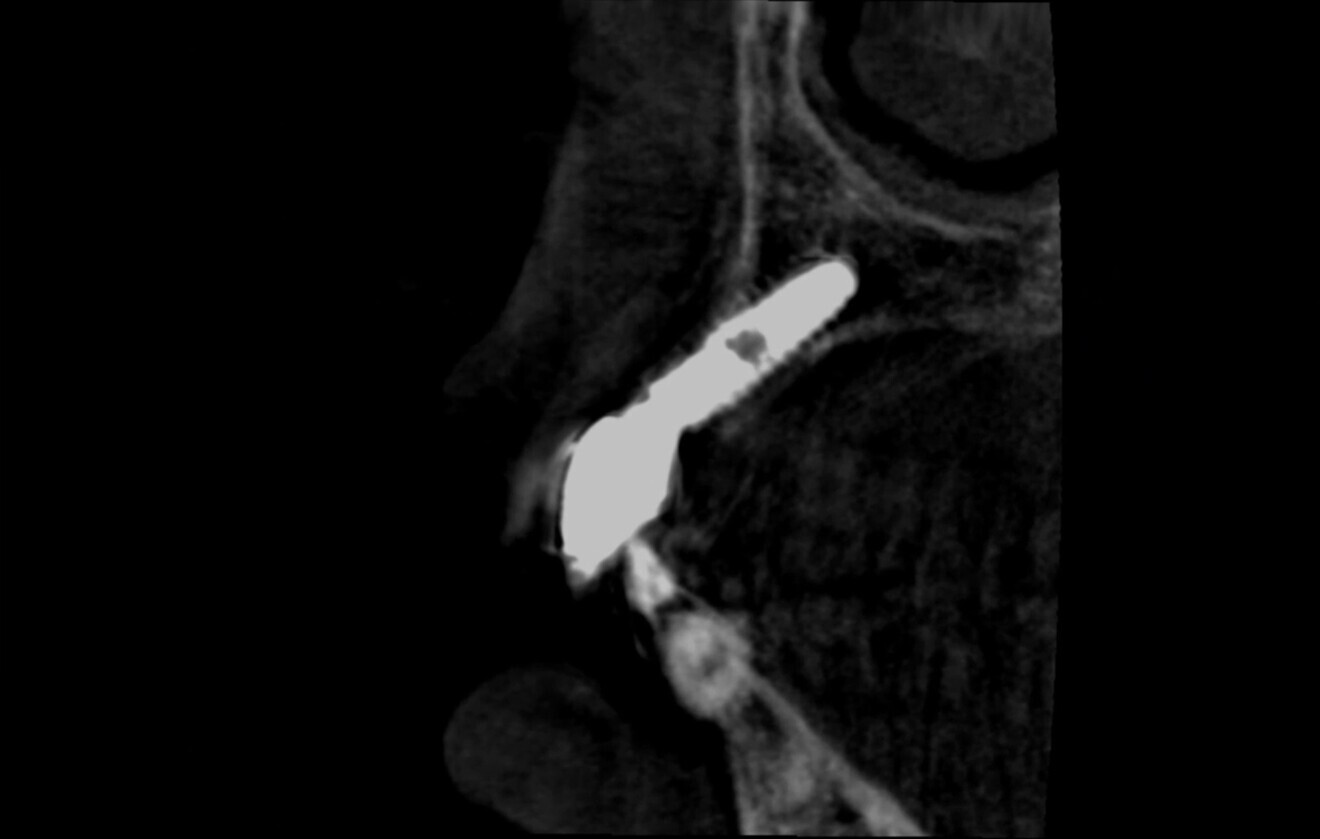

Fig. 3: Atraumatic implant removal using reverse technique.

At the initial visit, digital impressions were obtained using the Medit i700 scanner. Periapical radiographs and standardised intra-oral and extra-oral photographs were also acquired. A virtual diagnostic wax-up was generated to guide treatment planning. On the day of surgery, local anaesthesia was administered, and the implant was atraumatically removed using the reverse torque explantation technique. The surgical site was debrided and cleaned, and Type I collagen was applied to the socket (Fig. 3).